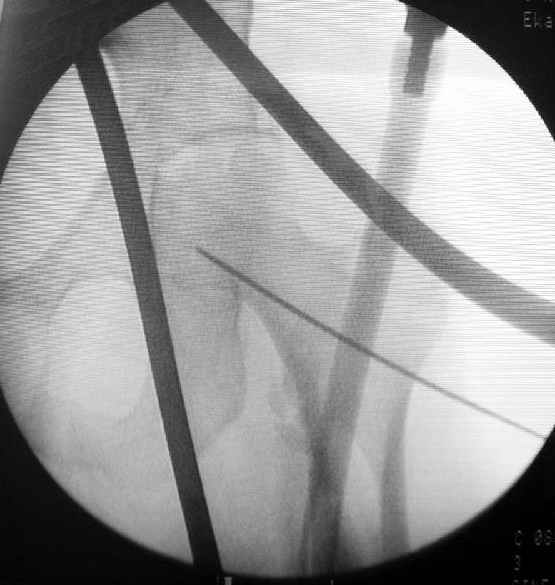

Как раз недавно у меня был примерный случай: больному 36 лет, поступил ночью, травма в результате мотоциклетной аварии, кроме чрезвертельного и спирального перелома левого бедра имеется переломы костей предплечья с этой же стороны. Скелетное вытяжение, а на следующий день больной про оперирован на ортопедическом столе с дистракцией. Чтобы не расколоть чрезвертельный перелом провели временную спицу ближе к переднему кортексу, из малого разреза костодержатель для репозиции, а фиксацию провели антиградным штифтом. Этапы операции на снимках.

Джолдас Кульджанов